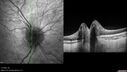

9 year old female She went for her annual eye examination, and they were concerned about the back of the eye. She has no visual obscurations and no headaches. She was found to have a HgB of 6.9 and anemia 12/10/21. She was iron deficient. She is taking iron. VA OD: Dsc20/80-2 PH20/25-2 NscJ1+2 VA OS: Dsc20/50 PH20/32 NscJ1+ IOP: TP: OD:14 OS:18

Optic Disc Drusen in a child (non Calcified)27 viewsFluorescein angiography shows no leakage00000